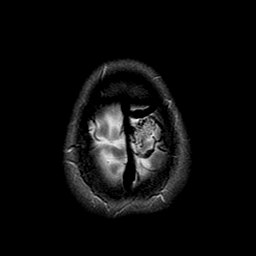

Vascular Malformation:T2-weighted MR #1 -- Slice #23

[Home][Help][Clinical] Slice 23